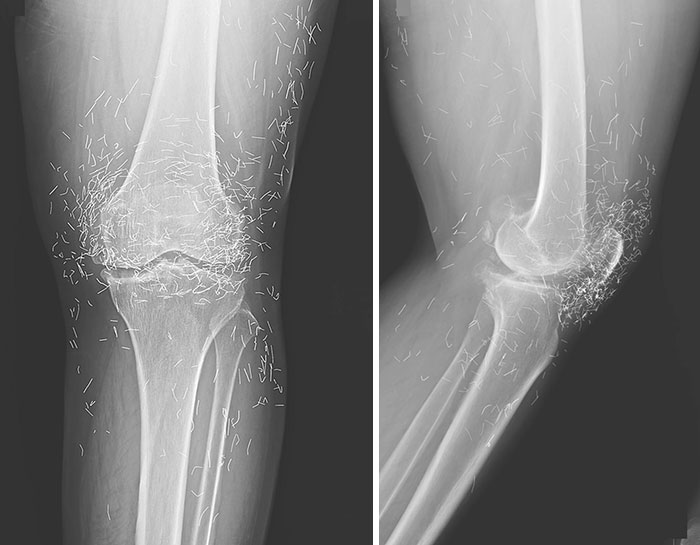

Ineffective Gold Thread Acupuncture Treatment For Osteoarthritis Of The Left Knee

Wait... Those squigly lines are gold threads? Can somebody please explain?